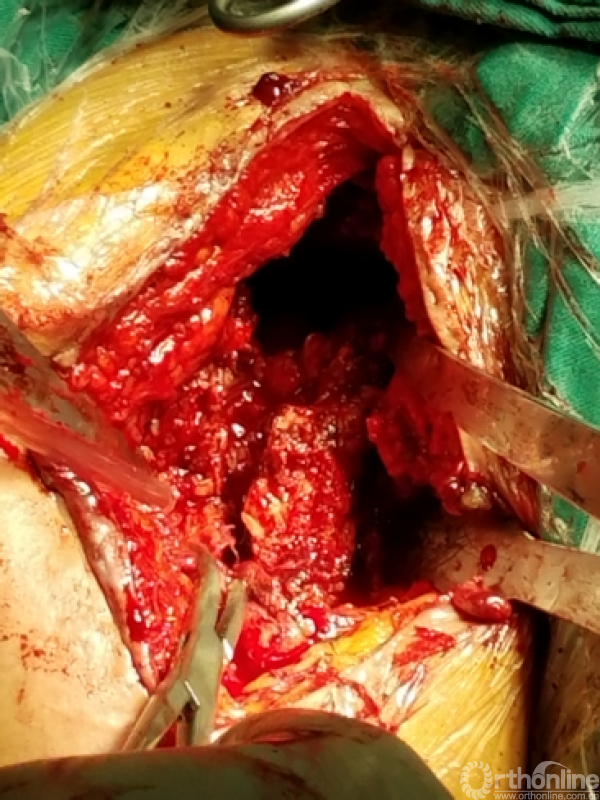

窦道周围见明显分泌物约10毫升

困难重重:

1、广泛粘连,解剖层次不清

2、广泛点状出血灶

3、分不清间隙

4、盂肱关节正常结构位置改变,关节囊瘢痕挛缩替代

5、屈曲外旋看不见关节间隙活动

咬出增生骨痂及清理瘢痕组织后显露出原肩袖缝线,杂乱,完整,表面见有脓性组织

瘢痕发硬,变性,周围包裹纤维软骨痂

由于解剖结构紊乱,头静脉已消失。旋肱后动脉,弓状动脉剥离时出血,位于外侧转弯处,行填塞止血。